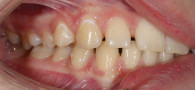

В клинику обратились родители подростка 16 лет с жалобами на «узкую» улыбку, наклон зубов вперед, щели между зубами у сына. После подробной диагностики врач предложила ортодонтическую коррекцию с помощью брекет-системы Damon Q.

Общая длительность лечения — 18 месяцев. В результате пациент получил ровные и красивые зубы, стал больше улыбаться.

Ортодонтическое лечение

Ортодонтическое лечение включало в себя установку брекетов с их регулярной коррекцией в стоматологии «Виртуоз». После окончания лечения пациенту было назначено ношение ретейнеров для закрепления результата. За 18 месяцев коррекции закрылись щёчные коридоры и промежутки между зубами, была выстроена правильная арка улыбки. Пациент получил зубы, о которых всегда мечтал!